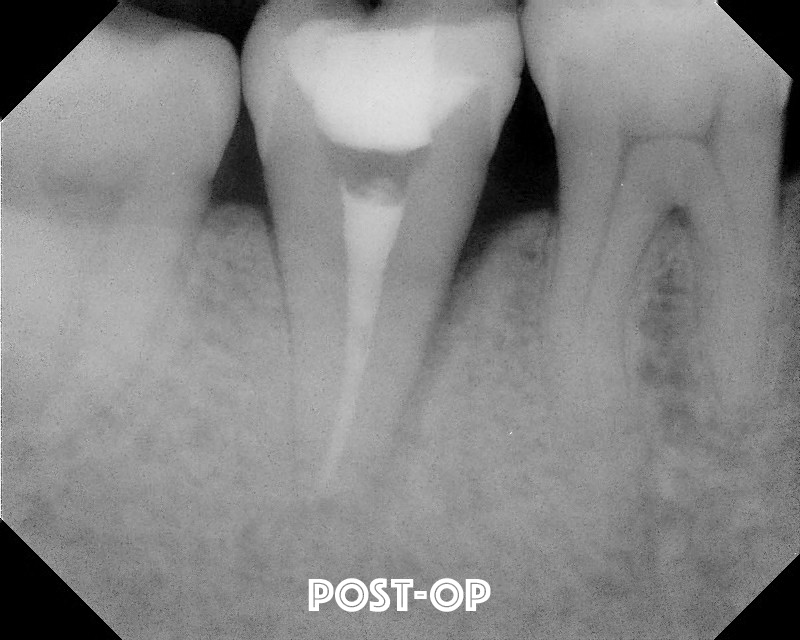

The root is kept moist and quickly examined for fractures.  None found, so we did retro preparation using and ultrasonic instrument.

An MTA retrofit is placed.

The tooth is replanted into the socket within 10 minutes of extraction.  Firm pressure is placed for an extended period of time. No splinting